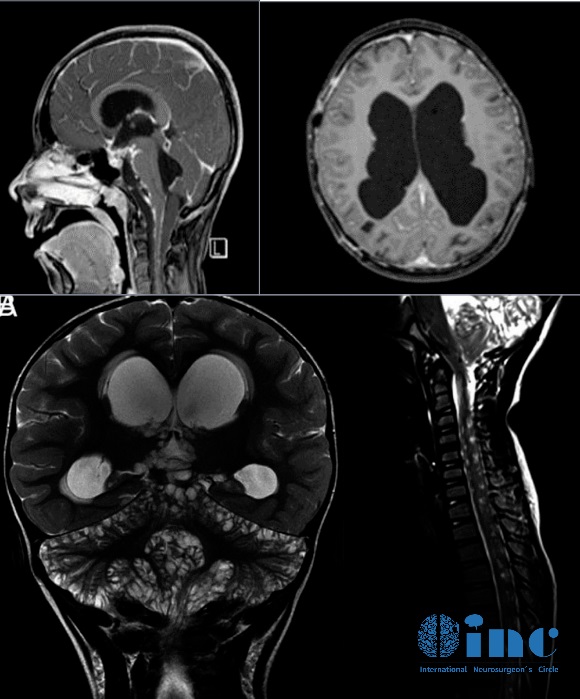

入院后,齐齐进行了脊髓及颅脑核磁共振检查。

脊柱磁共振显示脑膜弥漫性强化,脑膜覆盖多处结节性病变,以及实质内病变和结节性小囊肿。

颅脑磁共振序列可见脑膜明显强化,是脑干腹侧表面上的软脑膜。

小脑弥漫性可见多发囊性病变,特别是上叶正中区和上蚓部,可能导致脑脊液循环障碍伴继发性脑室扩张。

从文献中提取的一些图像说明了刚才提到的情况:增强的蛛网膜的病理性增粗,肿瘤的多个结节状定位,相关的脑积水。大脑的非强化局灶性囊性病变是由血管周围间隙的局灶性扩大造成的,也是因为脑脊液循环受阻而扩大。